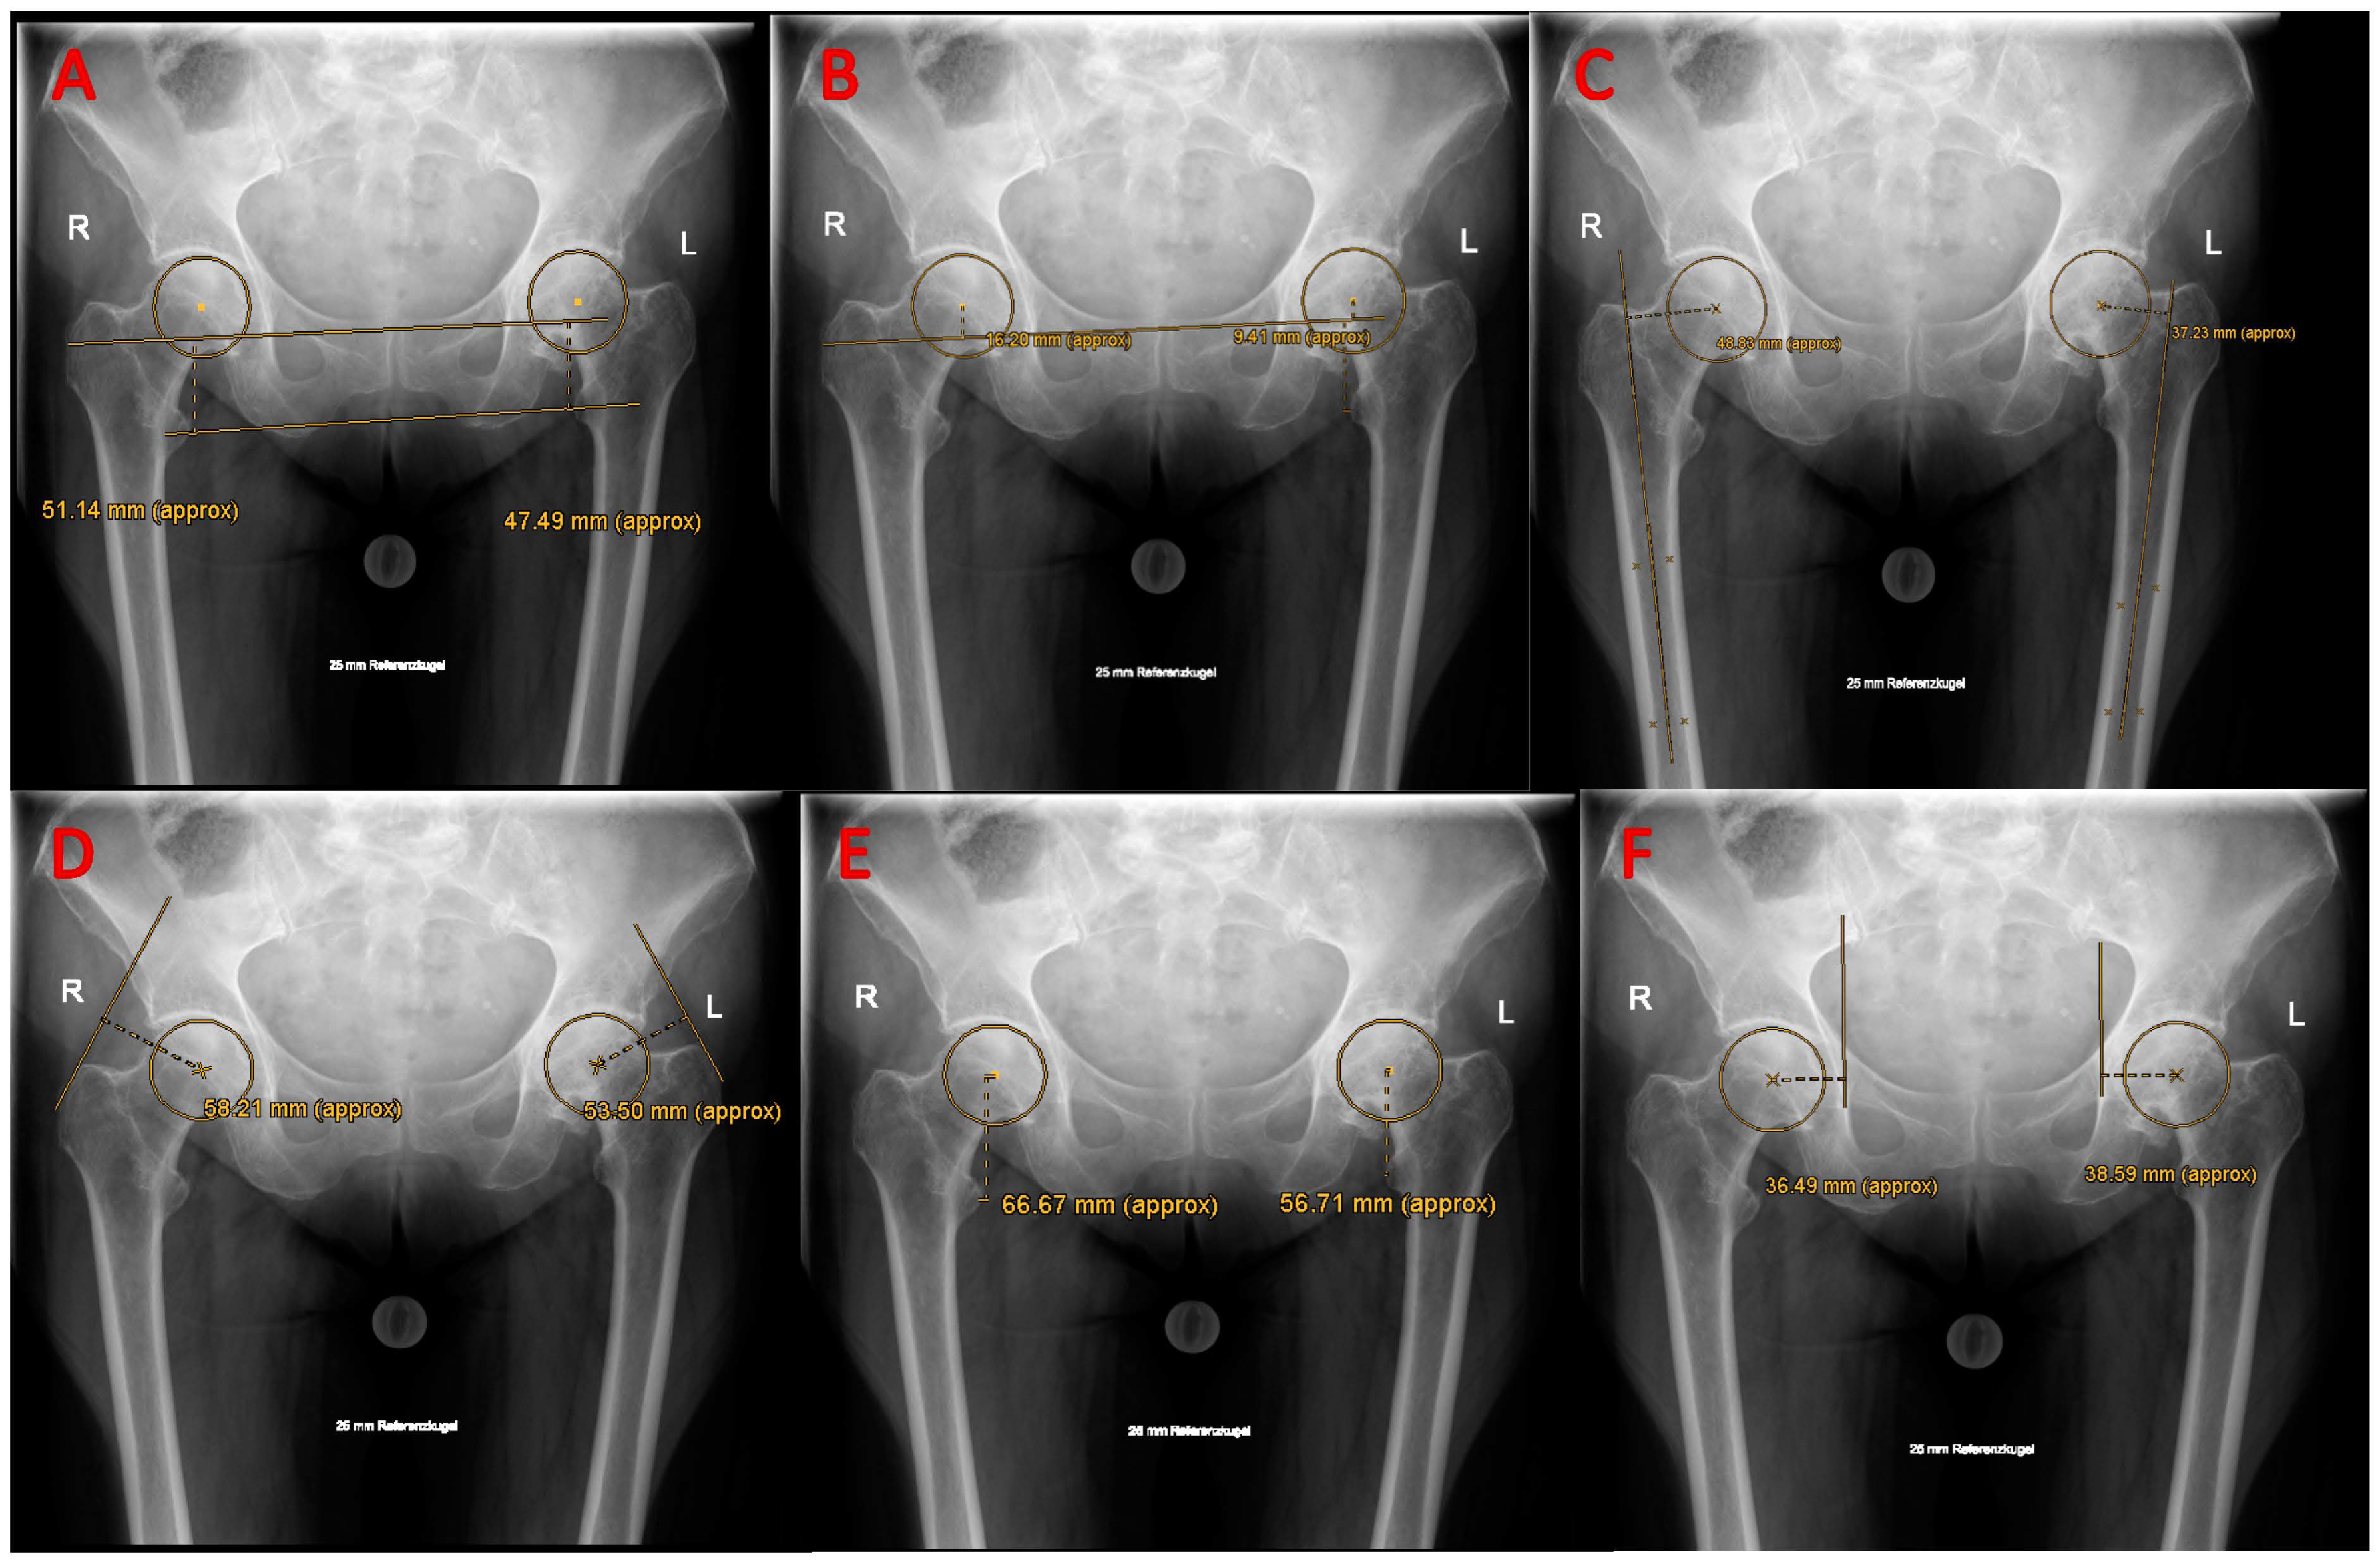

2.2. Radiological Assessment

3.1. Reconstruction of Hip Biomechanical Parameters

3.2. Component Positioning